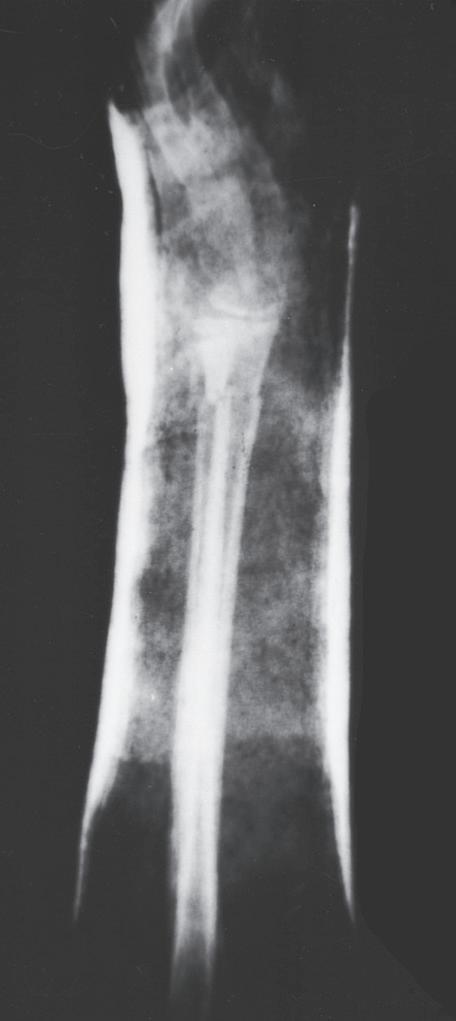

Fig. 1.8 (A) Anteroposterior and lateral radiographs of a 15-year-old boy who sustained a displaced transverse fracture of the diaphysis of his tibia. (B) Follow-up at 4 months shows abundant periosteal healing, although a portion of the fracture line is still evident. It is characteristic for pediatric long bone fractures to heal early with periosteal callus; secondarily, the diaphyseal cortex heals and remodels.

Fig. 1.2 Anteroposterior (A) and lateral (B) radiographs of a forearm in a 15-year-old male who underwent open reduction and internal fixation with plates/screws. The fracture healing demonstrates primary bone healing with rigid fixation. An anteroposterior radiograph of a forearm in a 5-year-old at the time of original cast immobilization (C) and at 10 weeks (D) with complete fracture union demonstrates secondary bone healing. The motion that occurs with secondary bone healing results in abundant callus formation.

Secondary healing results from treatment of fractures with less rigid methods (i.e., fracture bracing, casts). In secondary healing, more motion at the fracture site leads to lower

oxygen tension, and more cartilage is formed. Motion at the fracture site, the presence of a fracture gap, and an intact soft tissue envelope all encourage the formation of abundant callus (Fig. 1.2C, D). The increased diameter of the callus enhances biomechanical stability because the rigidity of the bone is proportional to its radius. The callus formed subsequently undergoes endochondral ossification. Ideal fracture treatment involves enough rigidity to ensure adequate vessel ingrowth, followed by progressive loading and motion to stimulate ample callus formation.36,40